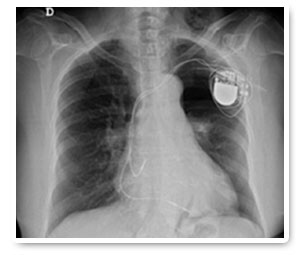

Un marcapaso o marcapasos, es un dispositivo electrónico diseñado para producir impulsos eléctricos con el objeto de estimular el corazón (generar contracciones cardiacas) cuando falla la estimulación normal.

Consta de varias partes, un electrodo o cable conductor y un generador de impulsos o marcapasos propiamente dicho, para que cuando estos impulsos, generados en el "generador o marcapasos" sean transmitidos a través del cable conductor al corazón para generar una contracción cardiaca.

Se realiza una pequeña incisión debajo de la clavícula izquierda o derecha y se introduce el cable a través de una vena cercana hasta la aurícula derecha y/o el ventrículo derecho (dependiendo del tipo de trastorno que se esté tratando. Posteriormente, cuando el cable esté en el lugar adecuado (se confirma mediante rayos X), se conecta al marcapasos y este queda alojado debajo de la piel. El procedimiento finaliza suturando la piel.